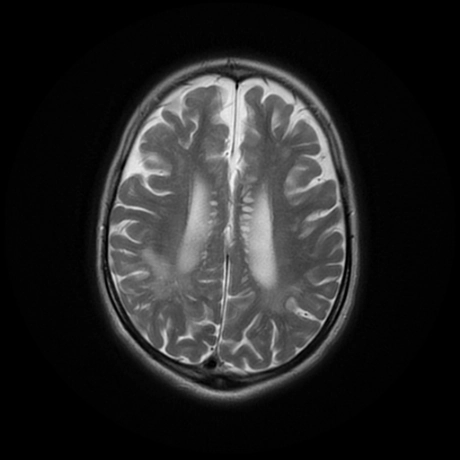

Bệnh não ty thể (Mitochondrial Encephalopathies -ME)

Rối loạn ty thể nguyên phát (Primary mitochondrial disorders - PMDs)

Các biểu hiện ở não của bệnh mucopolysaccharidoses (Cerebral manifestations of mucopolysaccharidoses)

Bệnh loạn dưỡng chất trắng tế bào hình cầu (Globoid Cell Leukodystrophy)/ Bệnh Krabbe

Bệnh Fabry (Fabry Disease)

Rối loạn Peroxisome (Peroxisomal Disorders)/Hội chứng Zellweger (Zellweger Syndrome)

Bệnh nước tiểu mùi si-rô phong (Maple syrup urine disease - MSUD)

Bệnh Canavan (Canavan Disease)

Bệnh loạn dưỡng chất trắng thượng thận liên kết nhiễm sắc thể X (X-linked Adrenoleukodystrophy)

Nhiễm toan glutaric type 1 (Glutaric aciduria type 1)

Bệnh Loạn dưỡng chất trắng thể não to kèm nang dưới vỏ (Megalencephalic Leukoencephalopathy with Subcortical Cysts - MLC)

Thoái hóa thần kinh với tích tụ sắt trong não (Neurodegeneration with Brain Iron Accumulation - NBIA)

Thoái hóa thần kinh liên quan đến Pantothenate Kinase (Pantothenate kinase-associated neurodegeneration - PKAN)

Huntington Disease - HD

Bệnh loạn dưỡng chất trắng dị sắc (Metachromatic Leukodystrophy - MLD)

Bệnh Wilson- Biểu hiện ở não bộ (Wilson Disease)